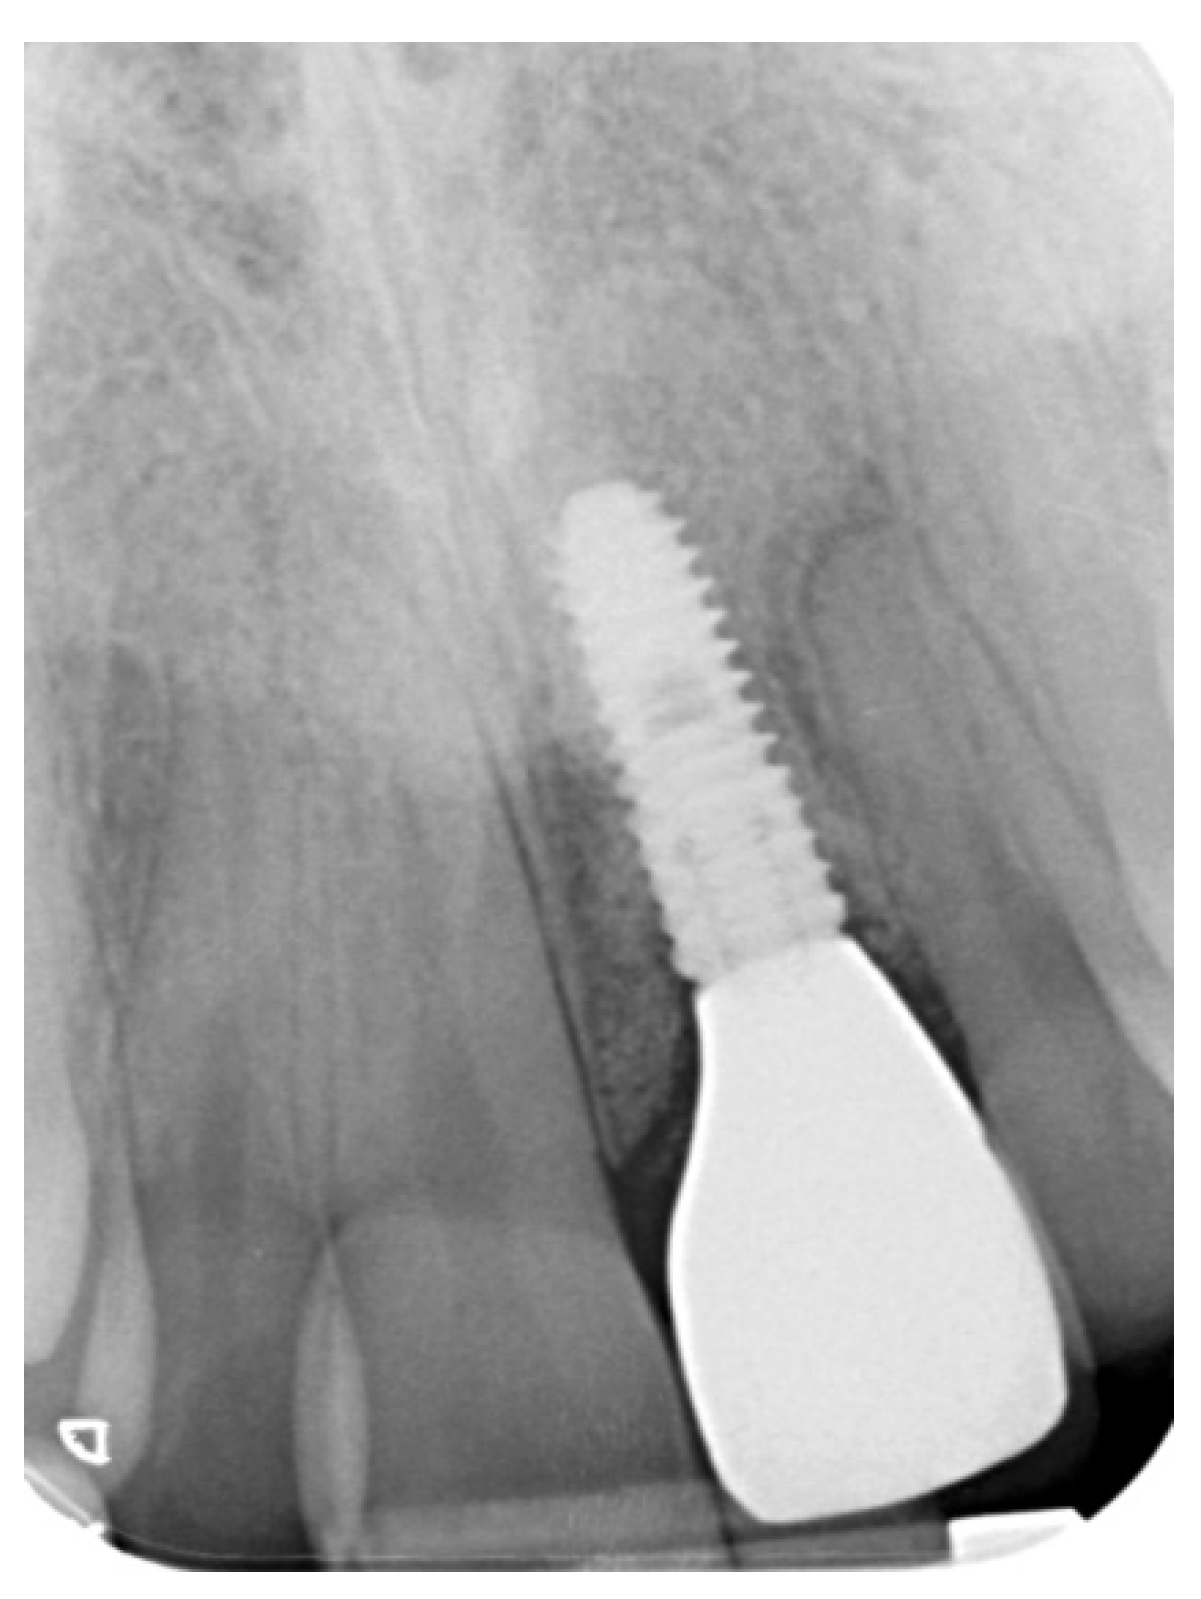

Tissue Recession around a Dental Implant in Anterior Maxilla: How to Manage Soft Tissue When Things Go Wrong?

2. Case Presentation